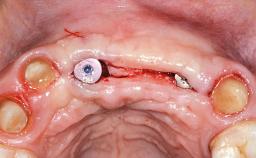

Replacement of Four Incisors with a Fixed Partial Denture on Two Narrow-Neck Implants after Implant Failure

| # of Implants | 2 |

| Bone Augmentation | Horizontal|Staged|Vertical |

| Augmentation Materials | Autogenous block(s)|Xenogenous|Membrane |

| Bone Volume | Deficient vertically or deficient vertically AND horizontally |

| Anatomic Risk | High |